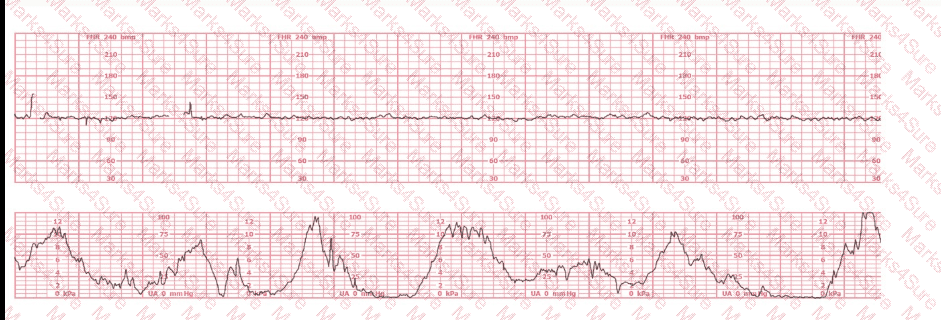

A woman at 38-weeks gestation is admitted to labor and delivery following a fall down the stairs three hours ago. She started feeling contractions in the ambulance. The fetal heart rate tracing shown is on initial evaluation and represents 25 minutes. This tracing is most consistent with a